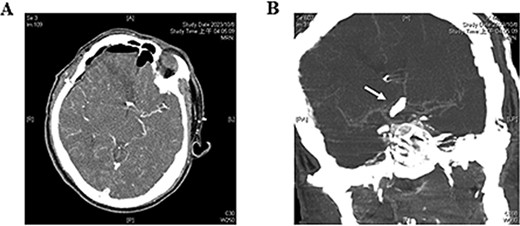

Four hours postoperatively, the patient experienced a generalized tonic–clonic seizure, requiring emergency intubation and sedation. Emergent post-operative brain computed tomography angiography confirmed that the right A1 segment was patent with no signs of intracerebral hemorrhage (ICH) or extradural hematoma (Fig. 3). Brain MRI, however, revealed a new infarction in the RAH territory (Fig. 4). To enhance perfusion, we maintained the blood pressure with a mean arterial pressure >65 mmHg and provided adequate hydration using normal saline. Antiepileptic medication was administered with levetiracetam 500 mg every 12 hours. Antiplatelet or anticoagulant medications were not given.

Postoperative brain MRI. (A) T2-weighted image shows a hyperintense area, indicating acute infarction of the recurrent artery of Heubner. (B, C) Findings are consistent with the abnormalities observed on the DWI and ADC images, respectively.